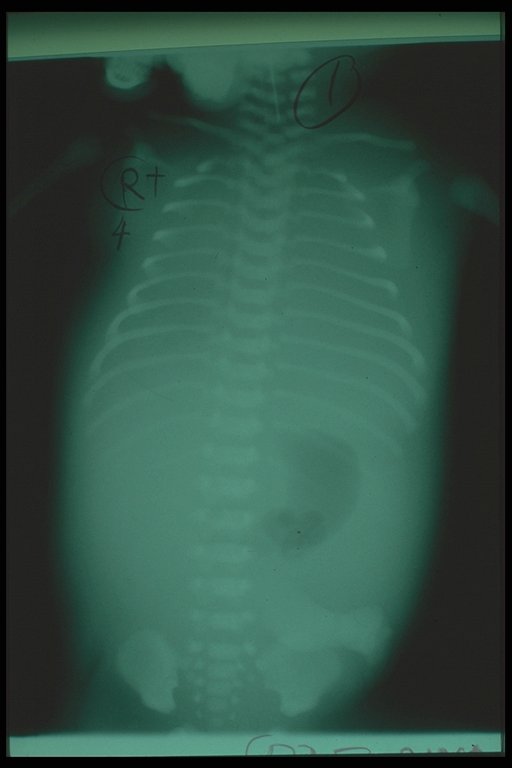

Three days after intercostal drainage of bilateral chylothorax. Both lungs expanded well. Generalized edema was still noted from the film.

Ten days after intercostal drainage of bilateral chylothorax. The baby could breathe without any assistant. Both lungs expanded well and less edema was noted.